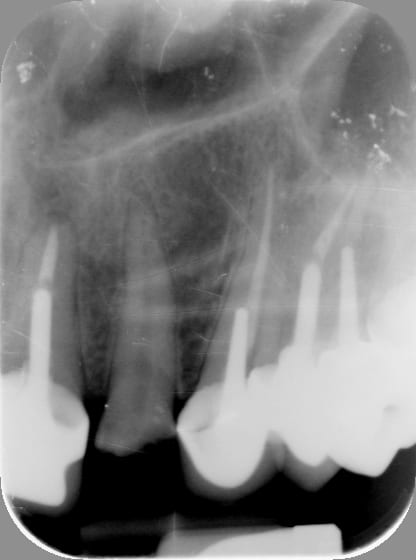

Pour la forme...il y a 15min...

Radio2 xuf6ph - Eugenol

Radio grxbfa - Eugenol